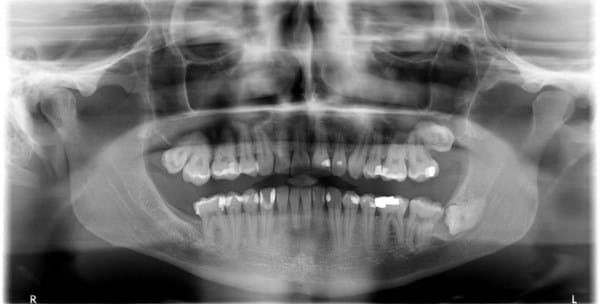

Caries dental tras radiografía boca completa

Me gustaría saber si tengo caries dental en esta radiografía ( En ese diente que esta pegado al cordal), unos dentistas me dicen que si y otros que no . Muchas Gracias . Un saludo.